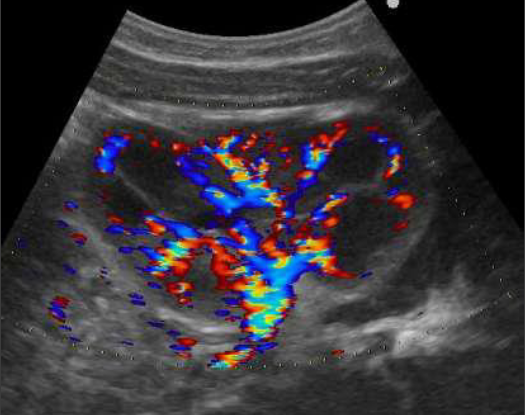

Imagerie des infections urinaires et du reflux vésico-urétéral

• Imagerie des infections urinaires et du reflux vésico-urétéral